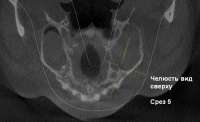

zub4sr3.JPG (82Кб, 1117x557)

ch5.JPG (44Кб, 745x458)

1-panorama.JPG (64Кб, 929x559)

>>574164

Как-то так. Это я сам на компьютере просматривал 3D и сделал как мне казалось лучшие срезы, на которых всё видно. Сам диск сейчас не знаю где.

Первый пик - тот самый зуб. Второй - срез прямо над корнями, вид сверху, соответственно. Третий - панорама.

Меня интересует главным образом, можно ли по такому снимку что-то определить, или деньги на ветер.

>>574166

Первый пик смотри. Самый дальний зуб тоже к пазухе лезет. Имхо пролечить зубы и гайморит уйдет

Алсо зуб на котором стоит перекрестие - вроде пролечен по типу каналов, но они пустые . Панорама как вижу старая. На ней все зубы стоят, да? А то пишешь , что что-то удалил, а там все стоит.

В общем 6 и 7й у тебя до пазухи доходят корнем.

зубб.JPG (10Кб, 454x366)

>>574250

>В общем 6 и 7й у тебя до пазухи доходят корнем.

Лол, это не шестой и седьмой (если ты про первый пик). Срез же. 6-7 по Y-координатам идут ближе к зрителю поэтому их не видно.

Это 4-й и 6-й. Но седьмой и восьмой, что на панораме, по моему тоже в пазухе корнями.

> На ней все зубы стоят, да?

не, тот с которого всё началось уже удален до снимка. 5-й ещё в детстве выдавило соседними 4-м и 6-м назад, поэтому он как бы был во втором ряду. Справа тоже, кстати, такая мутация, лол, но там всё нормально, если не считать большой кисты самой гайморовой пазухи.

Нарисовал пикрелейтед как было. Получается, что три зуба как бы соприкасались в одной точке. 5-й с 4-м по моему буквально корнями, так-как хирург говорил что чувствует как шатается 4-й пока он расшатывает 5-й.

Ладно, в общем, спасибо за ответы. Наверное всё же к стоматологу пойду первее, распечатаю на бумаге, скажу так то и так то, че делать, снимать повторно или идти к лору и снимать у него.

Аноним 18/02/17 Суб 15:18:07  574338

>>574336

>6-7 по Y-координатам

то есть если считать как было от рождения то 7-8, два последних.

нутыпонел

Я про панораму.

Сходи к лору . Скорей всего отправит к стоматологу конечно, но малоли что. Да и ,как говорил, вроде как скопы есть. Может трубку загнать и посмотреть чет